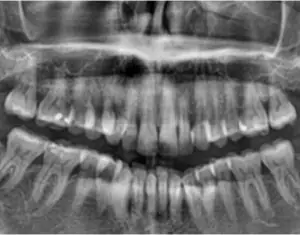

A Short Case Study: Odontoma or Osteoma?

A patient came in with pain on tooth No. 31. It was an abutment for a three-unit bridge. The diagnosis was necrotic pulp with acute